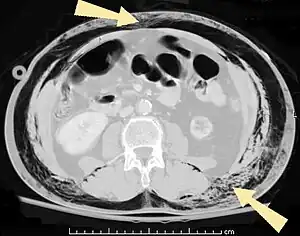

- Pneumatosis intestinalis, air or gas cysts in the bowel wall